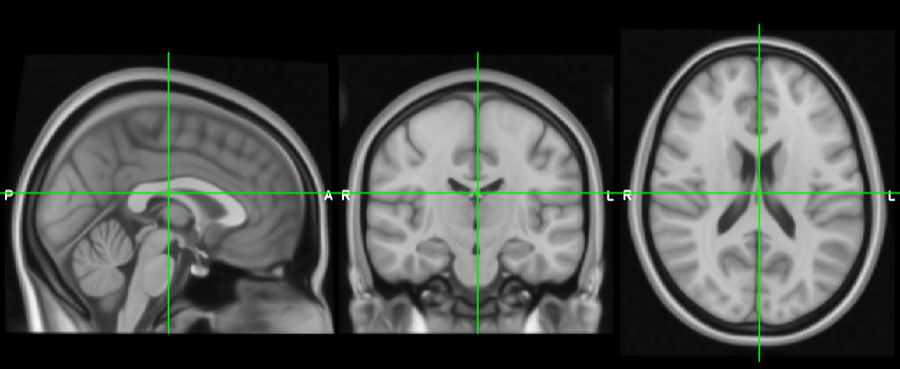

Ortho view

_images/ortho_lightbox_views_ortho.png

The ortho view comprises three canvases, which display your overlays along three orthogonal planes. For a NIFTI image which is oriented acording to the MNI152 template, these canvases correspond to the sagittal, coronal, and axial planes.

Ortho view interaction

You can interact with an ortho view in a number of ways:

• Click, or click and drag, to change the current location.

• Right click and drag to draw a zoom rectangle. When you release the mouse, the view will zoom in to that rectangle.

• Hold down the ⌘ key (OSX) or ⌃ key (Linux), and use your mouse wheel to zoom in and out of a canvas.

• Hold down the ⇧ key, and use your mouse wheel to change the current location along the depth axis for that canvas (i.e. to scroll through slices).

• If a mesh overlay is selected, hold down the ⇧ and click the mouse to select the mesh vertex that is nearest to the mouse click.

• Middle-click and drag, or hold down the ⌥ key and drag with the left mouse button, to pan around.

• Hold down the ⇧ key and the ⌘/⌃ key, then click and drag the mouse to adjust the brightness and contrast of the currently selected overlay. Moving the mouse vertically will adjust the contrast, and horizontally will adjust the brightness.

• Hold down the ⇧ key and the ⌘/⌃ key, then right-click and drag the mouse to select a region in the currently selected image. When you release the mouse, the image display range will be set to the minimum/maxmimum voxel intensities within the selected region.

• You can reset the view to its default zoom/pan settings by pressing the reset_zoom_icon button on the ortho toolbar, or selecting the SettingsOrtho view 1Reset display menu item.